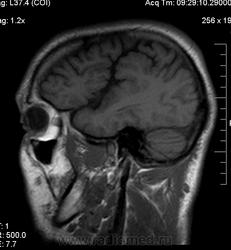

Мужчина 32 лет. Из анамнеза: перинатальное повреждение ЦНС, ДЦП, дизартрия, правосторонний верхний монопарез. С 16 лет приступы эпилепсии.

Аплазия прозрачной перегородки. Шизэнцефалия с открытыми краями в лобно-теменной области слева. Шизэнцефалия с закрытыми краями в лобной области справа? Утолщение коры по контуру расщелин и в области глазничной извилины правой лобной доли. Микрогирия? Гиперостоз костей свода черепа. Уважаемые коллеги, возможно я ошибаюсь, или есть еще аномалия?

На мой взгляд, полимикрогирия двусторонняя (конвекситальные отделы дорзальных отделов лобных долей и частично теменных, а также в базальном отделе полюса правой лобной доли) + закрытая шизенцефалия левой лобно-теменной области. Аплазия прозрачной перегородки (как признаки лобарной голопрозенцефалии).